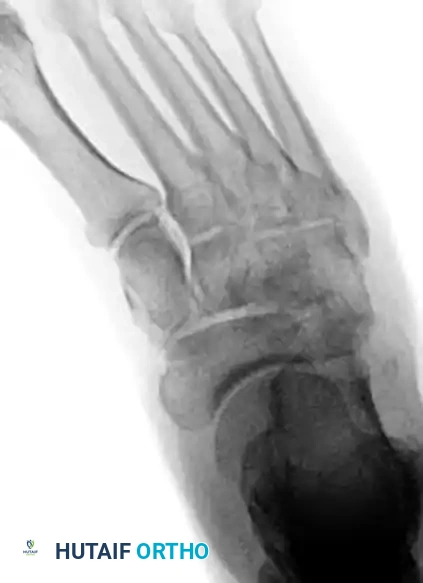

Standard non-weight-bearing radiographs often miss subtle instability. Weight-bearing radiographs are absolute requirements if the patient can tolerate them. If the patient cannot bear weight, a short-leg cast should be applied for 10-14 days, followed by repeat weight-bearing films.

Key radiographic parameters to evaluate:

1. The medial shaft of the 2nd metatarsal must align perfectly with the medial aspect of the middle cuneiform on the AP view.

2. The medial shaft of the 4th metatarsal must align perfectly with the medial aspect of the cuboid on the oblique view.

3. The 1st metatarsal-cuneiform articulation must show no incongruency.

4. The "Fleck Sign": Look for a small bony avulsion in the space between the medial cuneiform and the base of the 2nd metatarsal. This represents a bony avulsion of the Lisfranc ligament.

5. Evaluate the naviculocuneiform articulation for subtle subluxation.